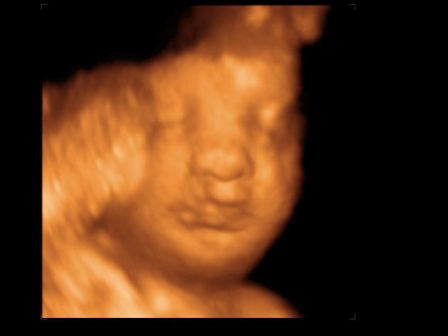

A másik, ma voltunk a 30 hetes UH-on és 4D-n.

Baba jól van, feje lent, lepényem elvándorolt, így már nem állja el a baba útját. Viszont meszesedik a lepényem, aminek még nagyon nem kéne, azt mondták, ez lehet a cukor miatt...

Kissrác nem mutatta meg magát, az egyik oldalát az arcának befúrta a lepénybe, a másikat eltakarta a kezeivel.

Végig le volt árnyékolva, alig készült kép, az is féloldalas.

Fél órát bökdöste a szonográfus, de nem mozdult, hanem kinyújtotta a nyelvét, aztán kiröhögött minket, na szép! :)

És a képek:

Kép Kinyújtja a nyelvét... Kép Aztán kiröhög... Kép És kb ilyen képek lettek :(